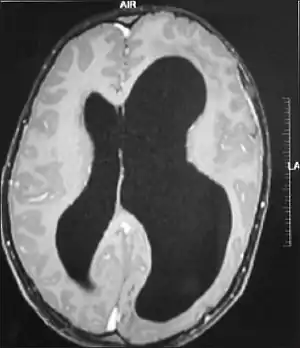

| Left-sided hemimegalencephaly in a person with neurofibromatosis[1] | |

It should be suspected in infants or children with intractable, frequent seizures.[4] On a CT scan, the affected part is distorted and enlarged.[9] It can be diagnosed prenatally, but a lot of cases go undiagnosed until seizures begin. Ultrasound can display asymmetrical brain hemispheres.[5]